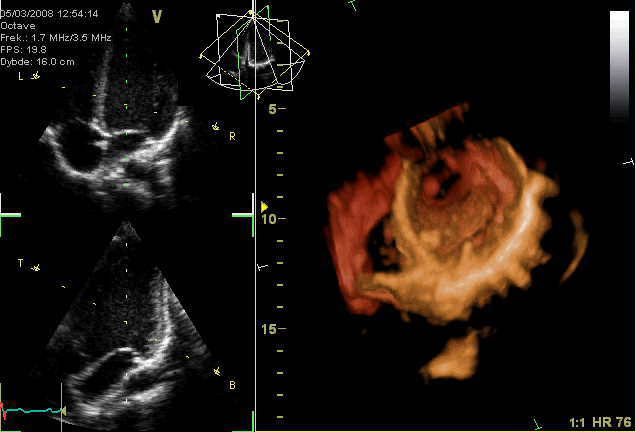

Ecocardiografía 3D

Una ecocardiografía muestra el corazón mientras late. También muestra las válvulas cardíacas y otras estructuras del corazón. En algunos casos, los pulmones, las costillas o los tejidos corporales pueden impedir que las ondas sonoras y los ecos suministren una imagen clara de la actividad cardíaca.

La ecocardiografía 3D (tridimensional) es una forma avanzada el ecocardiografía convencional, en donde permite reconstruir las imágenes en 2D a 3D, permitiendo un timpeo menor y un detalle mayor de las estructuras.